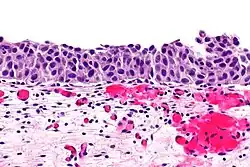

Inwazja warstwy mięśniowej raka urotelialnego

Kluczowym elementem wpływającym na rokowanie jest głębokość nacieku nowotworowego. Początkowo inwazja blaszki mięśniowej właściwej może przebiegać jako obecność pojedynczych komórek, klastry lub gniazda komórek w górnych warstwach blaszki mięśniowej właściwej, zwykle skojarzonej z infiltracją komórek zapalnych[79]. W późniejszych etapach inwazji obecne są klastry lub rozlane arkusze komórek nowotworowych w obrębie blaszki mięśniowej właściwej[79].